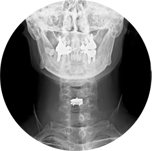

由於大都數患者都不願意戴頸圈,因此目前常的有PEEK支架帶有固定鈦合金的固定器的椎間植入器(如圖五,Zero-P, 目前我們使用進階版兩隻鈦釘的Zero-P VA),費用自費六萬多元,可健保申請,但除非有椎體部分切除者,否則健保很難申請通過。此器材優點是不用戴頸圈、價錢在許多私人醫療保險覆蓋範圍,缺點仍是該節被固定融合後的頸椎間活動度會受減少。

圖五